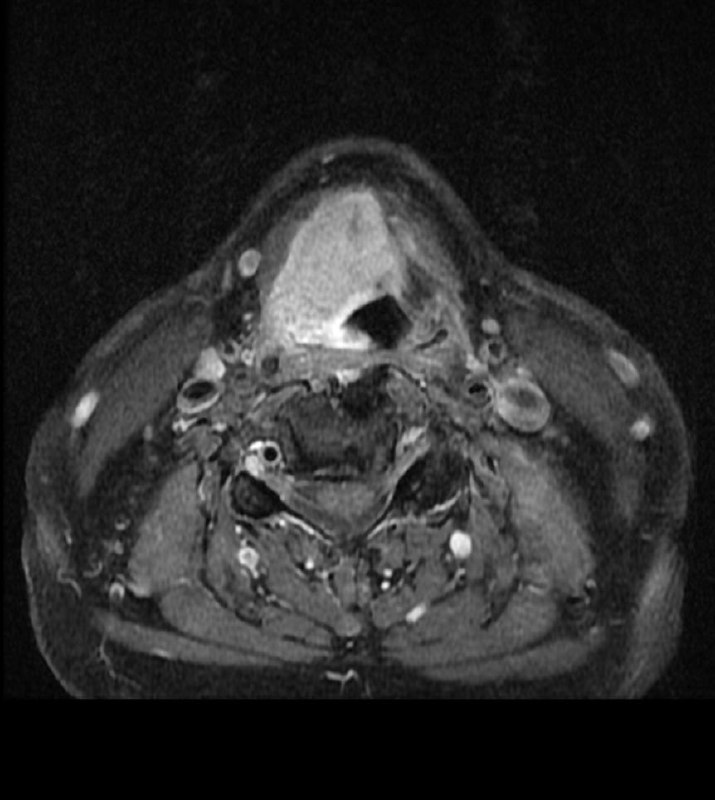

Больной 70 лет.

Выраженная осиплость голоса в течение полугода.

ЛОР-врачи ставят ларингит.

Делали биопсию: вот результат.

И какое здесь Т?